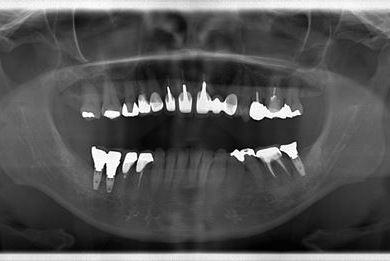

インプラント治療+セラミック治療

| 性別/年齢 | 女性 / 47歳 | ||||||||||||||||||||||||||||||||

| 主訴 | 前歯の黄ばみが気になる。 | ||||||||||||||||||||||||||||||||

| 治療方針 | インプラント・セラミック治療にて、機能的・審美的回復を行う。 | ||||||||||||||||||||||||||||||||

| 治療内容 | インプラント3本、ジルコニアフレームオールセラミッククラウン7本(ジルコニア用土台1本)、メタルボンドセラミッククラウン3本(メタルボンド用土台3本)、ハイブリッドセラミッククラウン3本、ハイブリッドセラミックインレー3本 | ||||||||||||||||||||||||||||||||